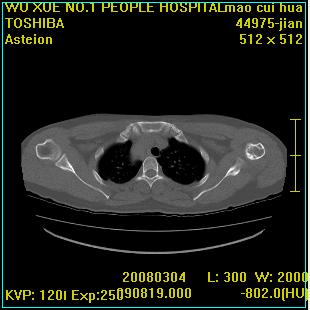

标题: CT12025:男,50岁,左肩活动受限半年。 [打印本页]

标题: CT12025:男,50岁,左肩活动受限半年。

肩关节骨质破坏呈小囊状,其周软组织轻度肿胀,余未见异常。

考虑:肩袖损伤。建议mri。

左侧肱骨头密度不均匀,高低混杂,周围软组织略肿胀,考虑结核性病变。

左侧肱骨头密度不均匀,高低混杂,髓腔密度稍高,周围软组织略肿胀,肌间隙模糊,考虑慢性骨髓炎可能。密切结合临床!